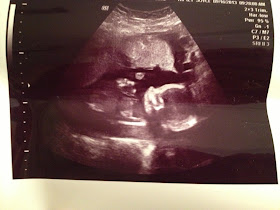

It's starting to feel more real now with my growing belly... I'm still feeling good, just tired. It's also stating to feel more real because yesterday, we found out that in less than five months, we'll be having a baby BOY! We couldn't be happier. It was so cool to see everything on the ultrasound and wonderful to hear that he is healthy and growing just as expected. He was moving around a ton at first, but then fell asleep. :)

Other than the one time at the doctor, I haven't felt any movement. I found out at my last ultrasound that I have an anterior placenta, so there is a cushion between my stomach and the baby. This will make it harder to feel little kicks and movements until a little later...